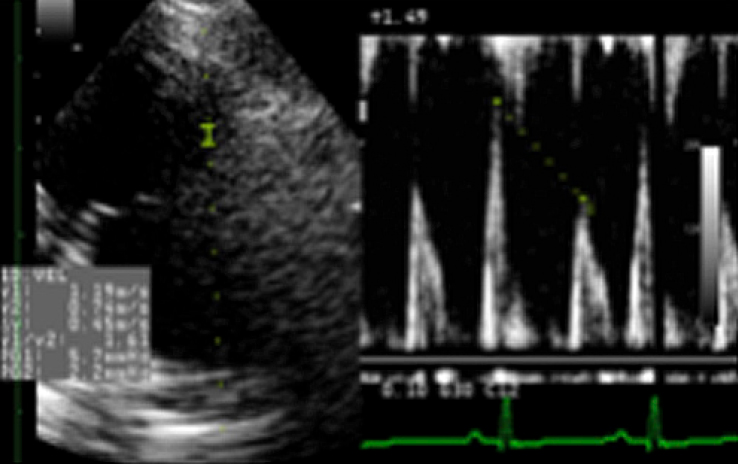

超音波検査

心臓の超音波検査をすることで、心臓の弁の動きや心臓の各部屋の大きさ、筋肉の厚さなど心臓の内部まで詳細に把握する事が可能です。また、心臓内を流れる血液の早さを測る事で、心臓の機能の厳密なモニターが可能です。心臓の何処がどのように大きくなっているのか、血液の流れはどうなのか、はっきりと把握することが、適した治療につながります。

右側傍胸骨四腔断面

心臓の4つの部屋を描出します。

それぞれの大きさや筋肉の評価をします。

LA/AO

左心房と大動脈の大きさの比較。

心臓の拡大の程度を探ります。

カラードプラ

血液の流れる向きを色で示し、逆流やジェットを明らかにします。

流速の計測

弁を流れる血液の早さを測り、血流の異常を探ります。